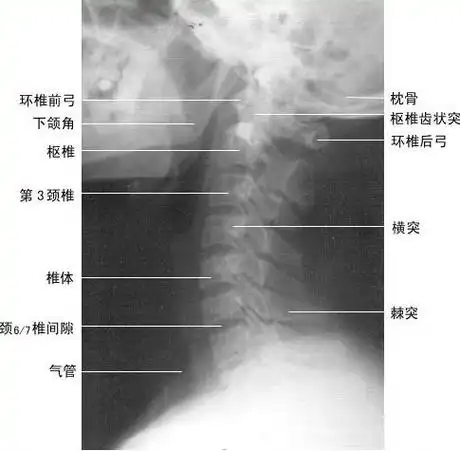

颈椎侧位(图)